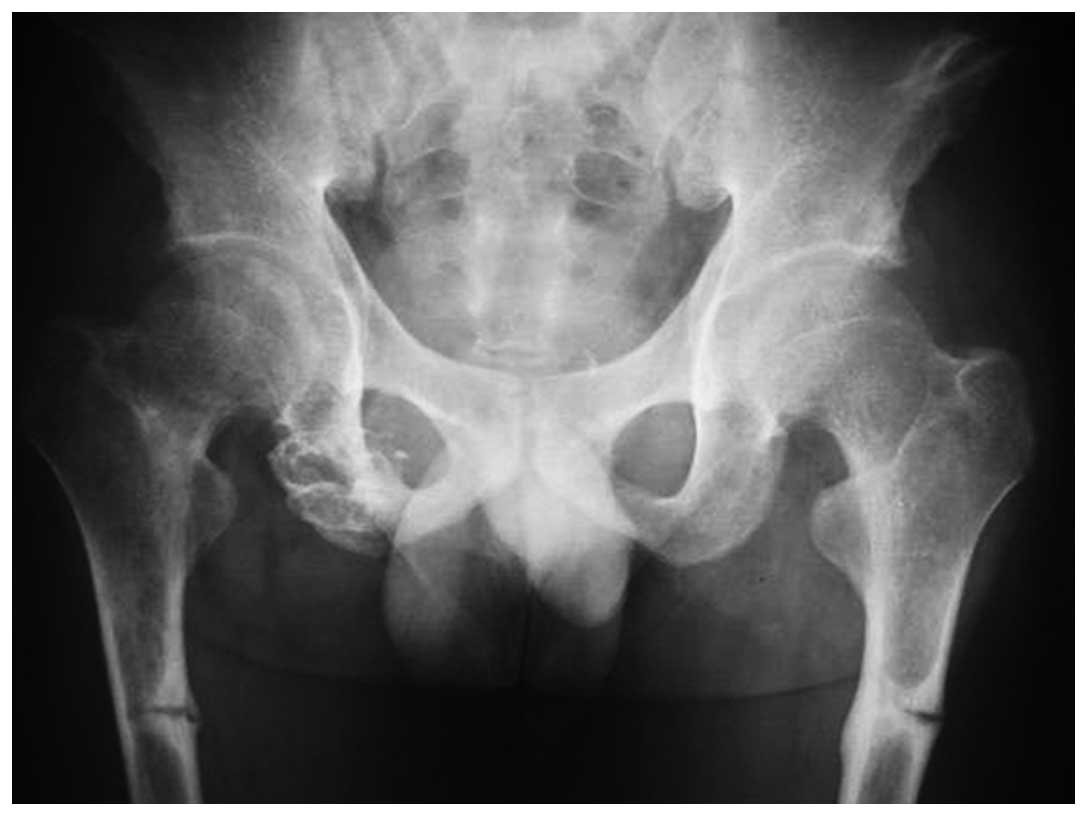

Темное пятно на рентгене бедра - фото презентация